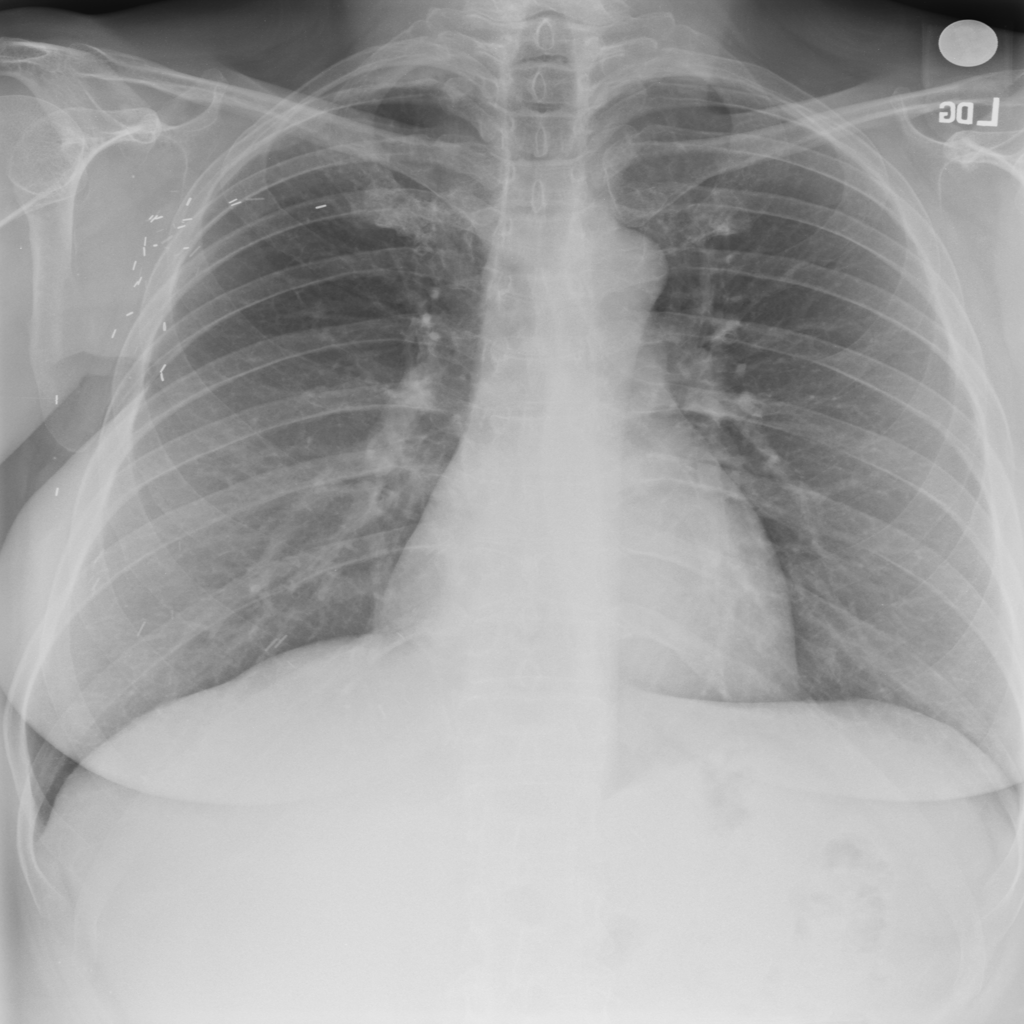

PAT-E960 · IMG-002Fibrosis

PAT-E960 · IMG-002

PA